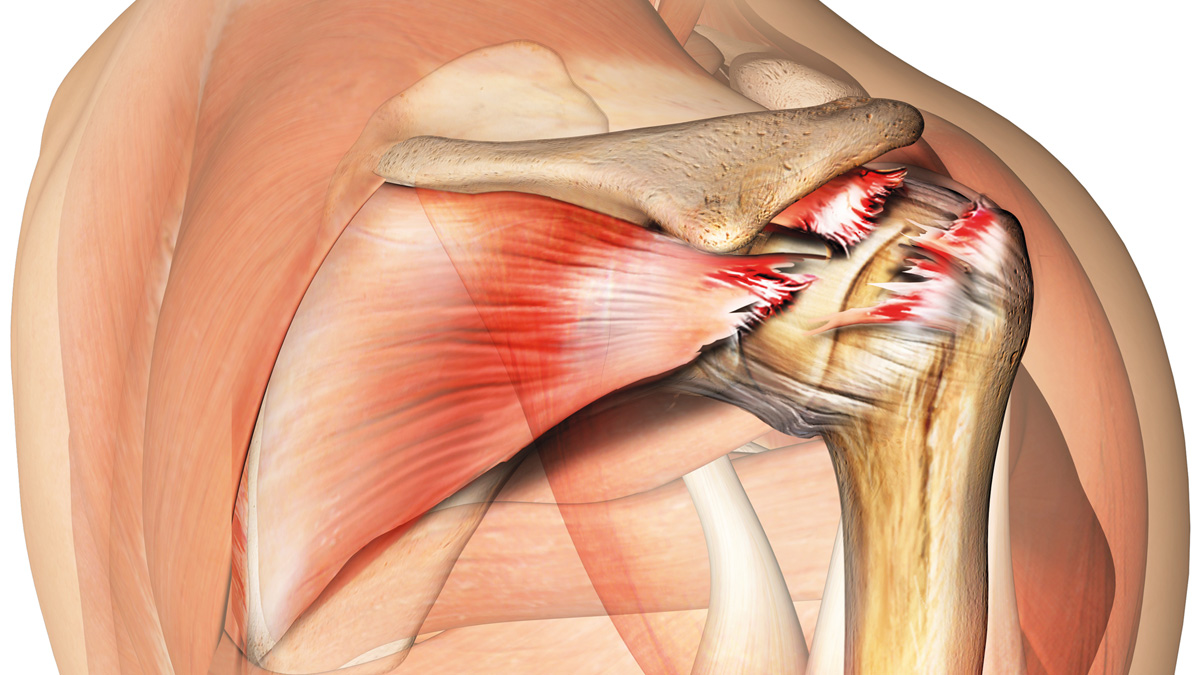

Фотографии мышц ротаторной манжеты плеча